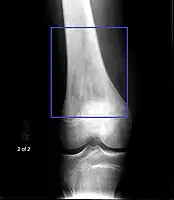

Osteosarcoma of the distal femur